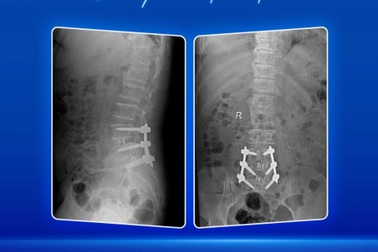

Điều trị thoát vị đĩa đệm nhiều tầng cột sống thắt lưng với công nghệ O-arm, định vị 3DThay vì trải qua cuộc mổ hở lớn, bà H. 66 tuổi được các bác sĩ tại khoa Ngoại thần kinh (BV ĐKQT Nam Sài Gòn) phẫu thuật xâm lấn tối thiểu qua hệ thống O-arm, công nghệ định vị 3D điều trị thoát vị đĩa đệm nhiều tầng L4L5, L5S1.